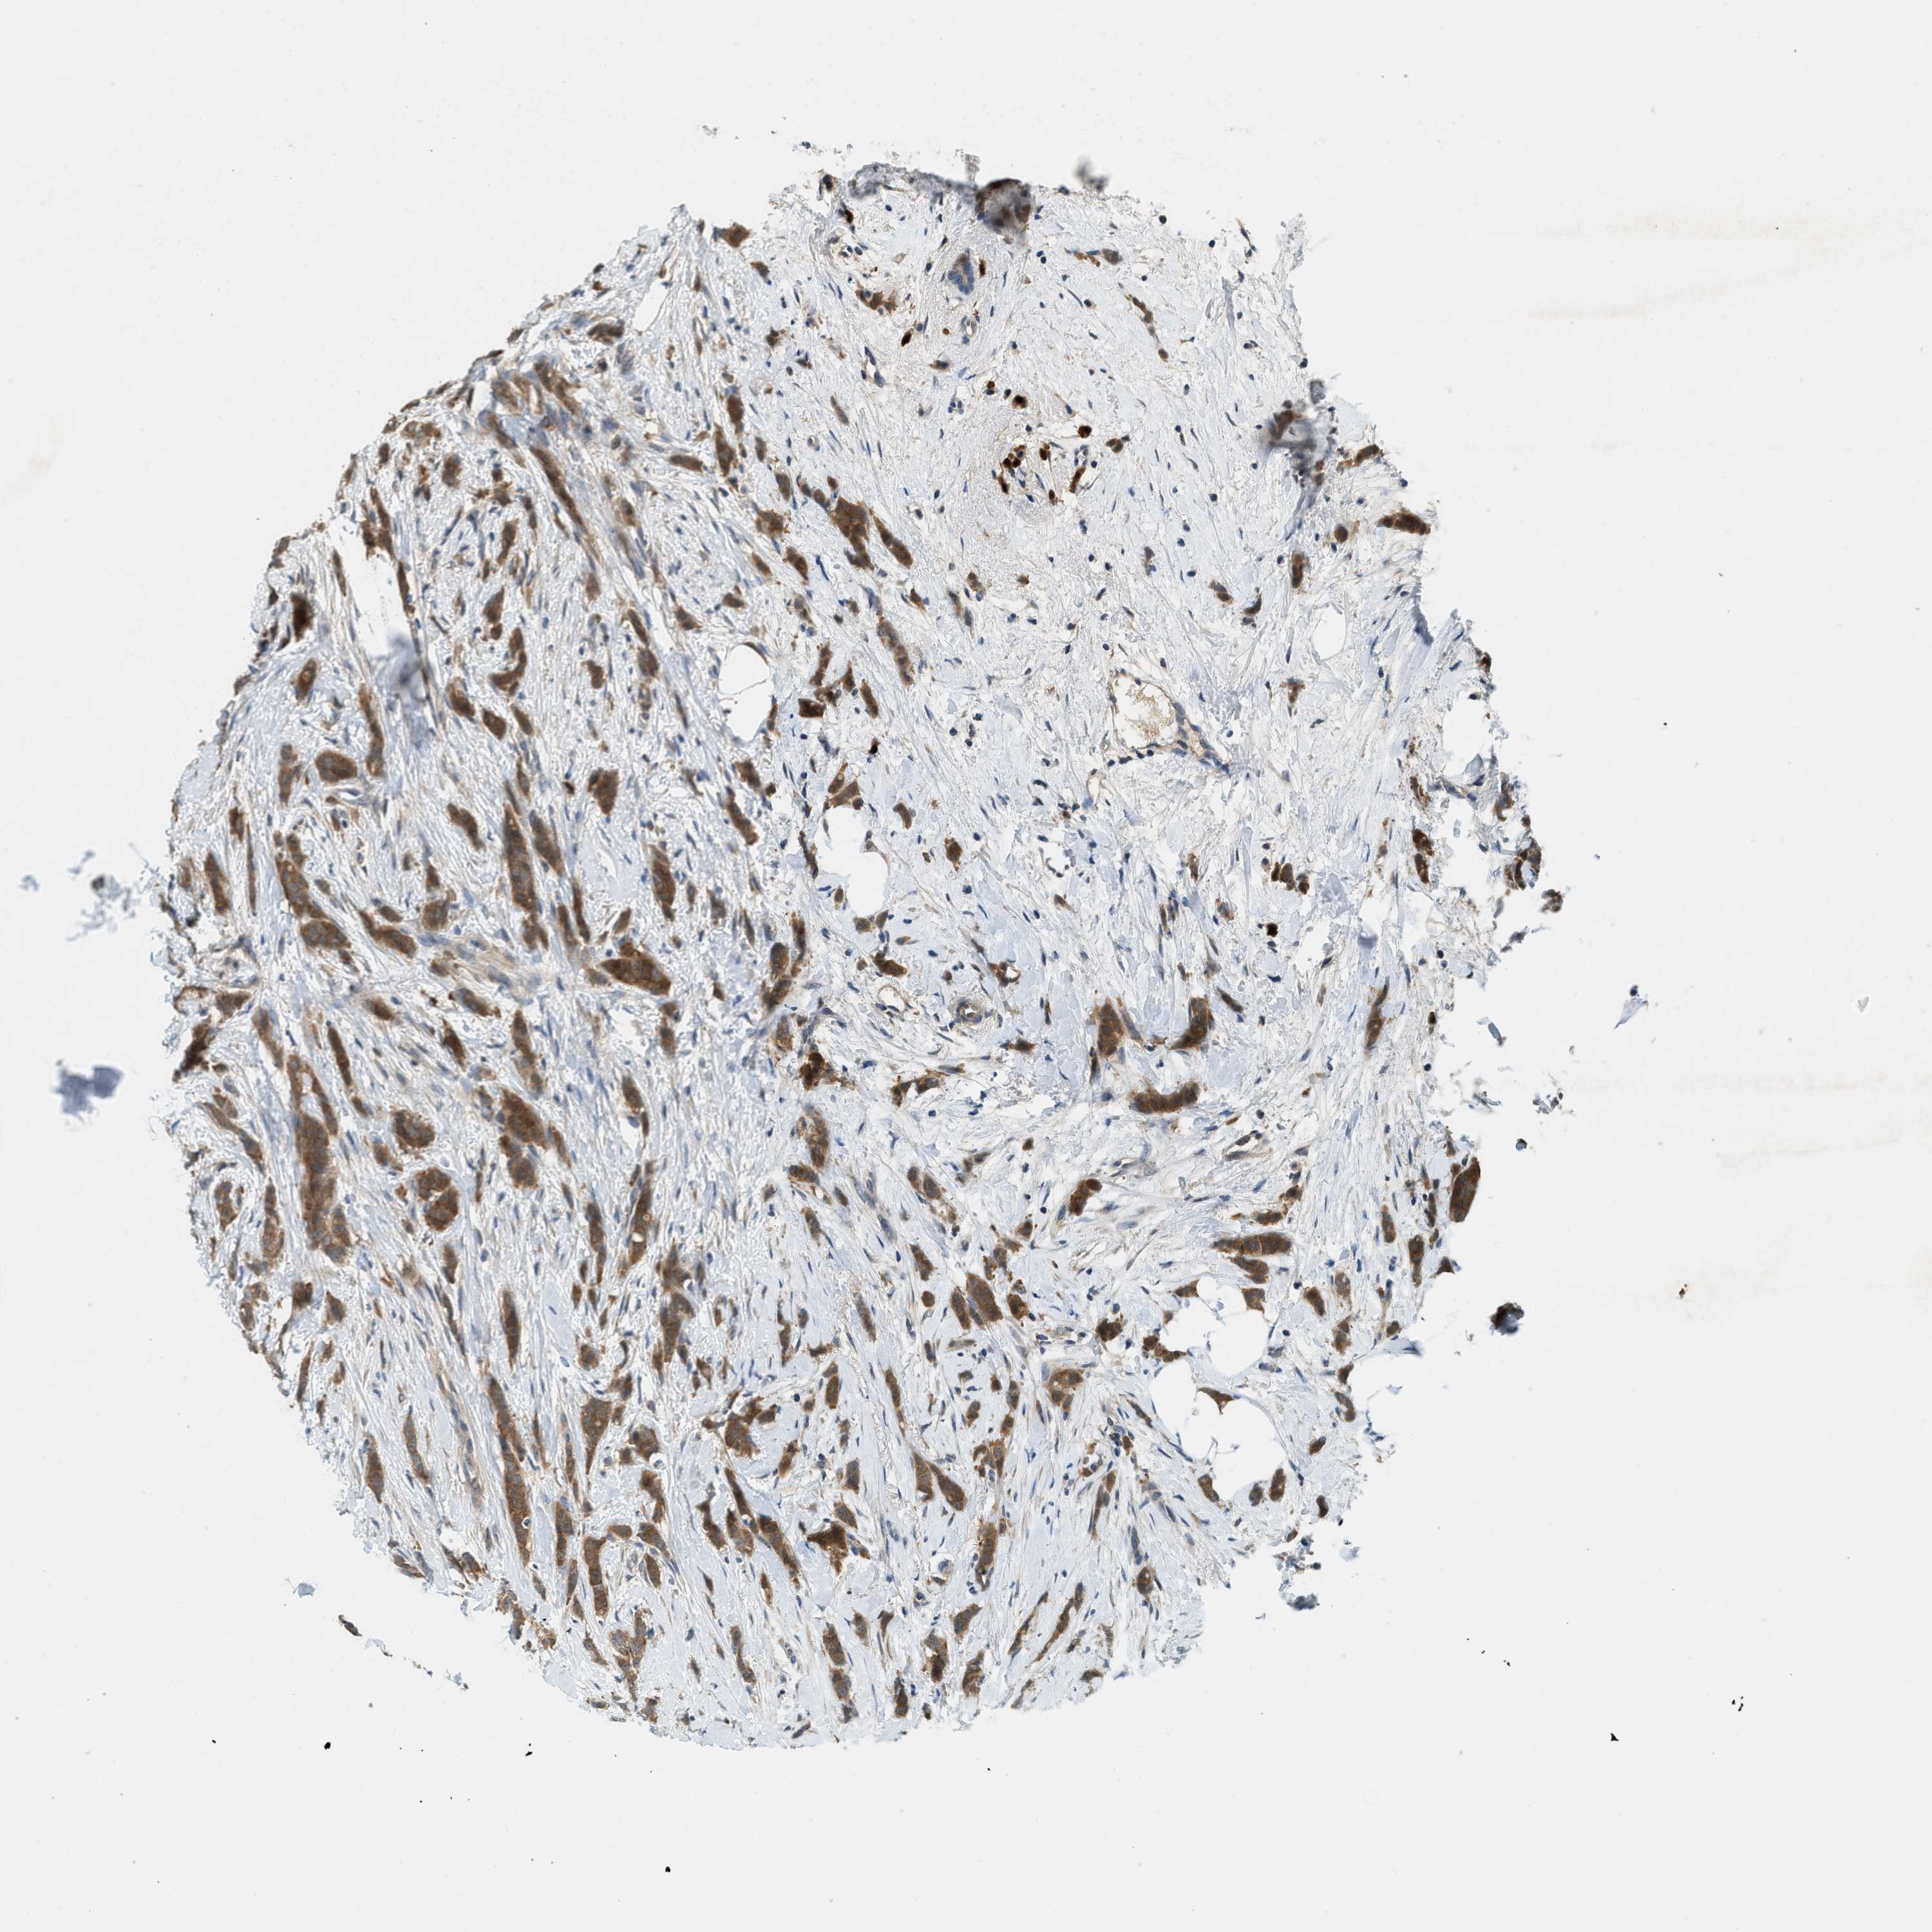

CANCER BREAST CANCER Show tissue menu

BRCA TCGA BRCA VALIDATION PROTEIN EXPRESSION